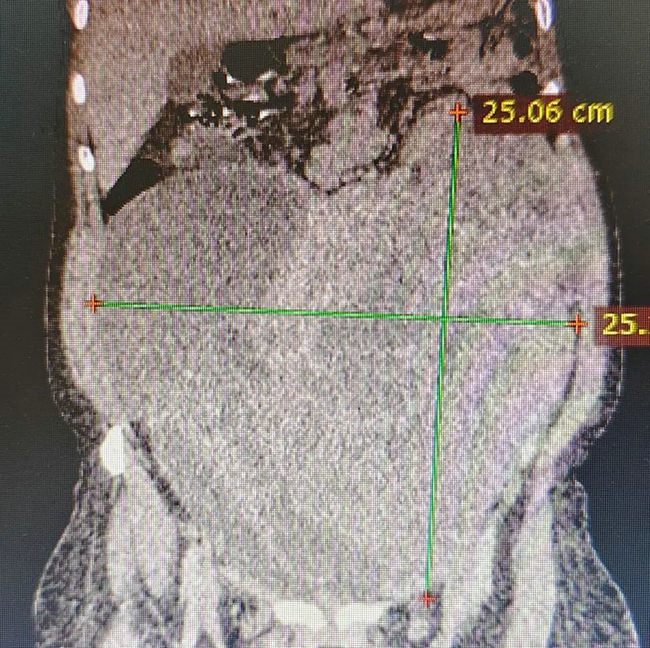

由于当地经济条件和医疗水平落后,很多患者无钱医治疾病,有的肿瘤患者肿瘤组织甚至长满腹腔,年幼的孩子肺脓肿能够穿破胸腔至体表,鼻窦炎的儿童炎症能蔓延到颅内……医生的缺乏也导致诊断报告几个月迟迟出不来,感到痛心的同时,他加班加点,加快影像诊断,马不停蹄地阅片、出报告,用了不到两周时间将前期累计的患者悉数完成报告。